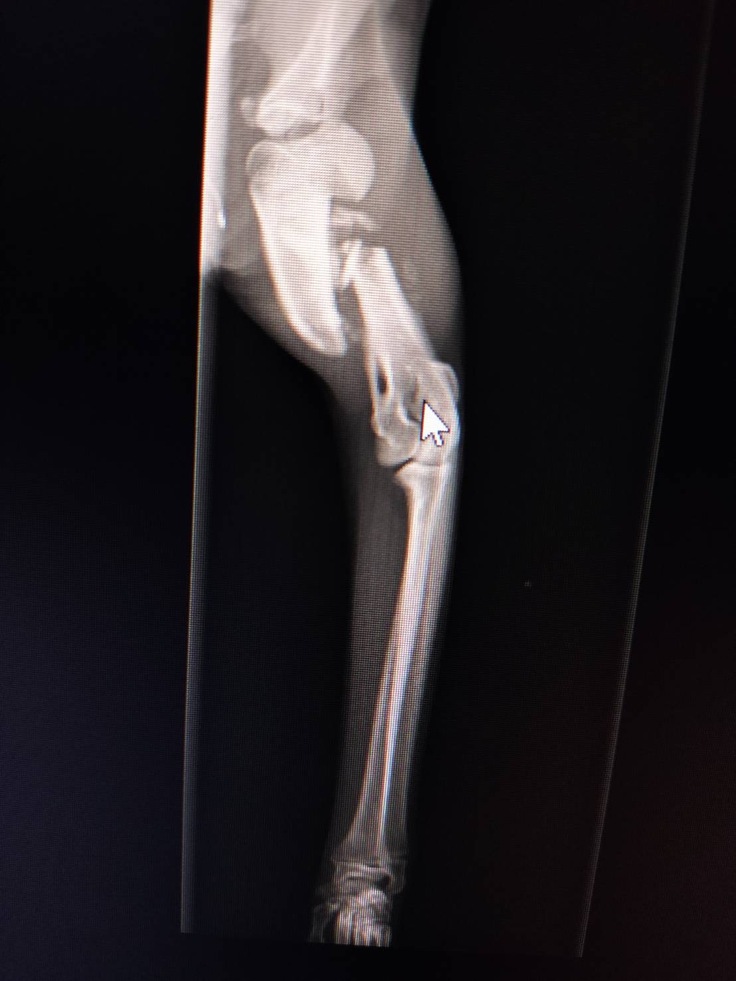

足先が麻痺している…

骨は大丈夫…

ボッキリ折れた大腿骨

すでに骨がずれたまま、くっつき始めてる